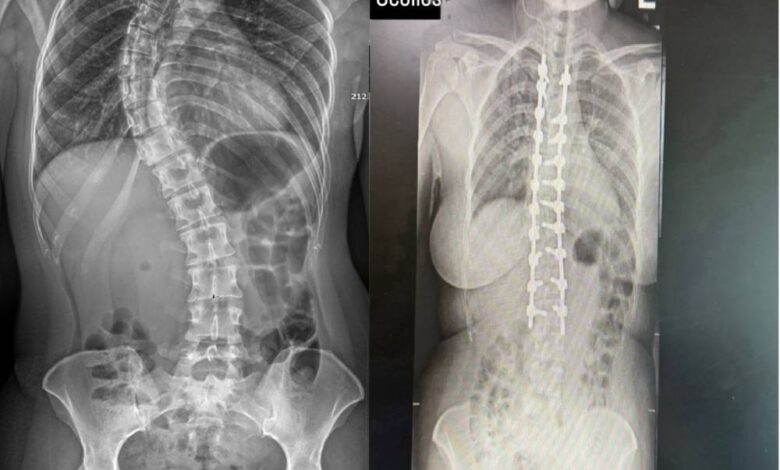

«المستشفى السعودي الألماني» ينهي معاناة مريضة بعد 30 عاماً

حقق مركز جراحة العمود الفقري في مستشفى السعودي الألماني دبي، إنجازاً طبياً متقدماً، بعد نجاحه في إجراء